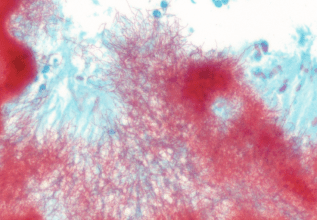

b) Gram stain: Gram positive filamentous organisms seen. (Colour of gram stain appears very atypical due to fixative).

a) H&E stain b) Gram stain